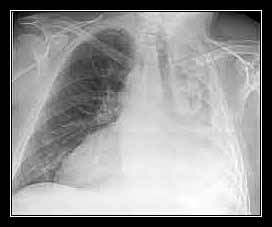

Mất âm hô hấp khu trú: bóng mờ co kéo trên phim X-quang. Xẹp phổi từng phần đôi khi rất khó nhìn thấy trên phim.

- Xẹp thùy giữa: hình trên phim phía – bên có giá trị chẩn đoán;

- Xẹp thùy dưới: co rút sau bóng tim.